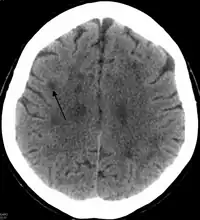

In HDLS, there is enlargement of the lateral ventricles and marked thinning or weakening of cerebral white matter.[6] The loss of white matter is caused by myelin loss. These changes are associated with diffuse gliosis, moderate loss of axons and many axonal spheroids.[1]

Neuroimaging

Standard MRI scans have been performed on 1.5 Tesla scanners with 5 mm thickness and 5 mm spacing to screen for white matter lesions in identified families. If signal intensities of the MRI scans are higher in white matter regions than in grey matter regions, the patient is considered to be at risk for HDLS, although a number of other disorders can also produce white matter changes and the findings are not diagnostic without genetic testing or pathologic confirmation.[2]